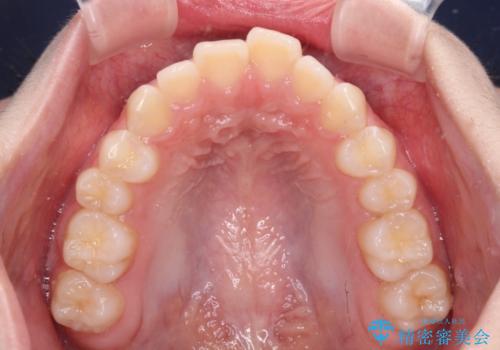

- 前歯のデコボコを気にして来院された高校生の患者様です。

捻れた前歯が前方に飛び出している点も気になっており、目立たない装置を希望されたため、インビザラインを用いて矯正治療を行うこととしました。

上下ともに少し捻れが残っていたため、治療の継続を提案しましたが、本人も親御さんも満足とのことで、治療を終えました。

捻れの改善により突出感も改善されました。